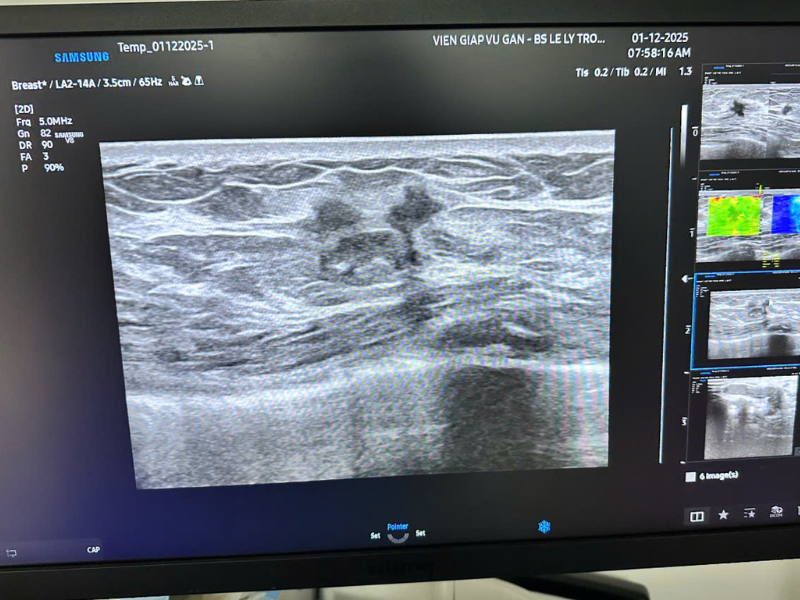

Hình ảnh siêu âm vú của chị N được chụp bằng máy siêu âm Samsung V8

Thế nhưng niềm vui ấy nhanh chóng biến thành lo lắng khi bác sĩ phát hiện nhiều khối u nghi ngờ ác tính ở tuyến vú.

Trước đó hơn một tháng, chị đã tự sờ thấy một khối nhỏ ở ngực. Nhưng vì nghĩ “để lúc khác kiểm tra cũng được”, chị tiếp tục trì hoãn. Chính sự chần chừ này khiến chị vô tình bỏ lỡ cơ hội phát hiện bệnh ở thời điểm thuận lợi nhất.